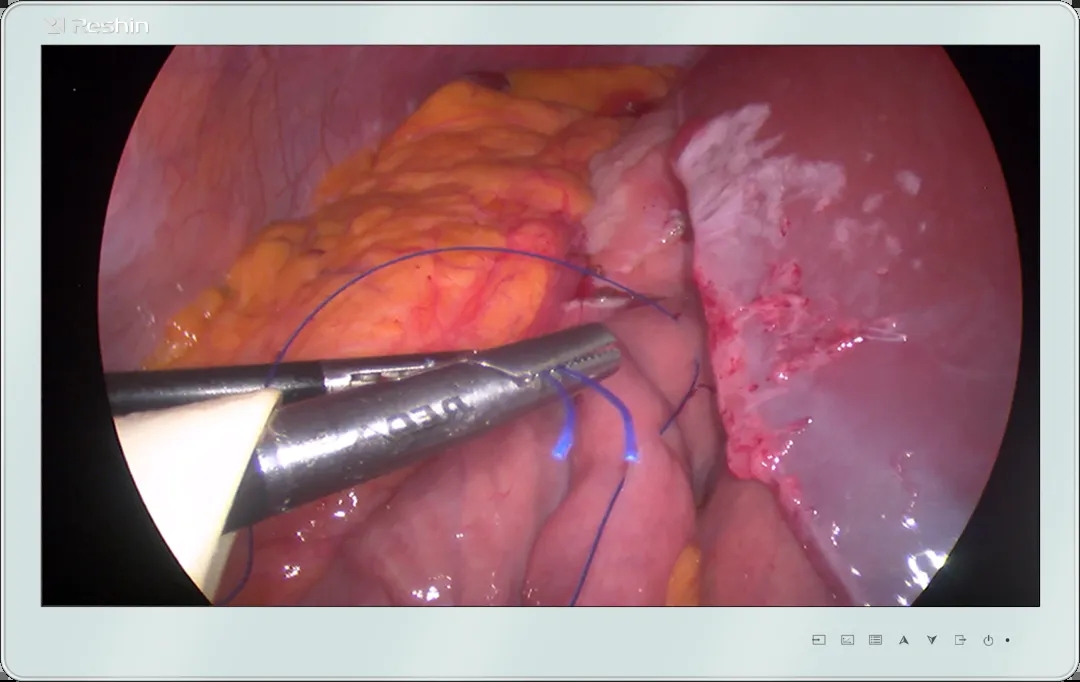

内窥显示器作为内窥影像的最终显示载体,承载着外科医生“第三只眼睛”的重要角色,是呼吸内镜介入诊疗的重要工具之一。睿显手术显示器采用IPS高清、全镜面设计屏幕,具备高色彩还原度,高对比度、高亮度等显示特性,为介入手术过程提供真实还原影像,优化医生操作体验,提高患者服务质量。

手术显示器具备更高的色彩还原度和更广的可视角度,确保医生在不同角度都能看到真实还原影像,保证手术过程中的图像质量。手术显示器具备高对比度、高亮度,能够提供层次分明、细腻真实的影像画面。优化医生操作体验,帮助医生更加清晰地观察病灶和准确地操作手术器械,给患者提供更好的服务体验。